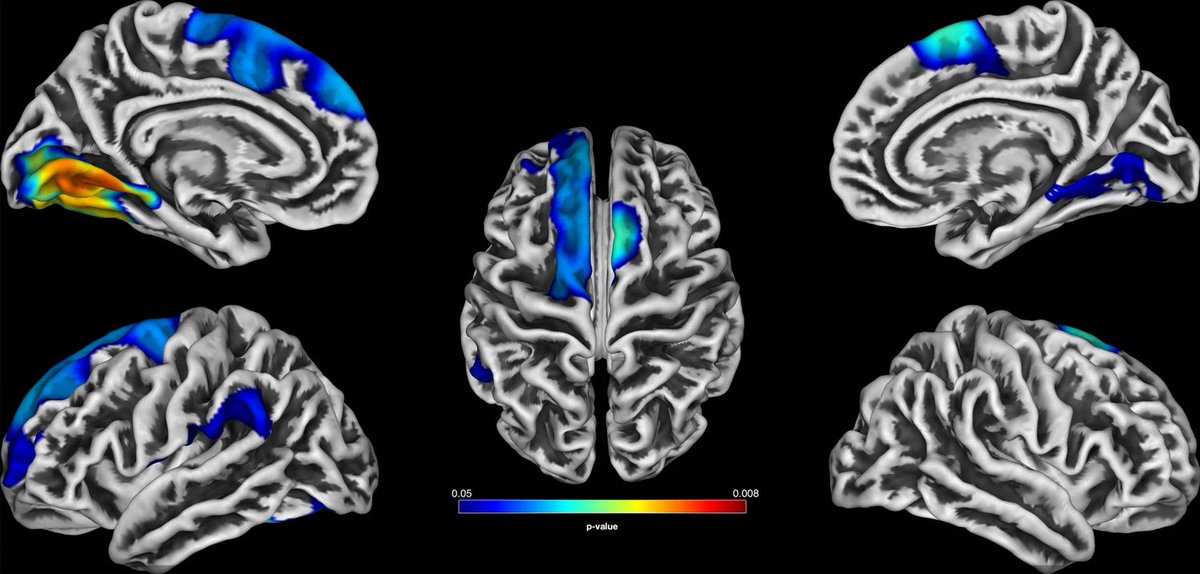

Super excited to share our molecularpsychiatry paper on shared GMV alterations across MDD, BD, and SSD🥳. Loved working with Dr. Katharina Brosch and all other colleagues of #FOR2107. Results below ⬇️ #ScienceTwitter #neuroscience

🚨new paper by #FOR2107. We showed transdiagnostic dimensions of lifetime psychopathology that were associated with GMV, CT and genetics. Findings underscore the need for dimensional approaches cutting across categorical diagnosis. TranslationalPsychiatry nature.com/articles/s4139…